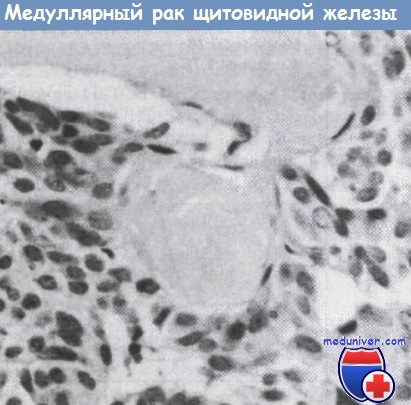

Фотографии опухоли медуллярной аденокарциномы

Раздел: Снимки-откровения